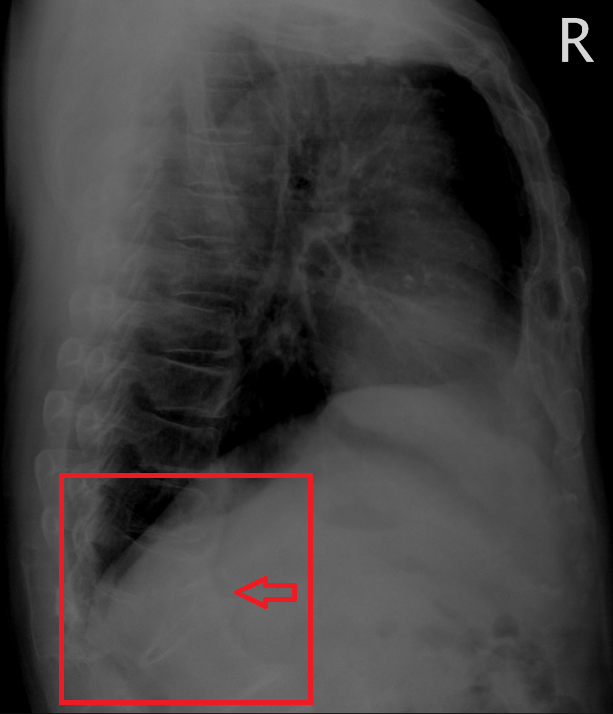

이차 고혈압 검사시 우연히 발견된 척추 압박 골절 소견, 어릴때 낙상에 의한?

http://blog.naver.com/ejercicio/220939683256 상기 환자 5일 혈압약 투약 후 내원, 이차고혈압 검사 시행 혈압 174/104 심전도 동율동, 59/min x-ray 정면; 심비대 소견 x-ray 측면...